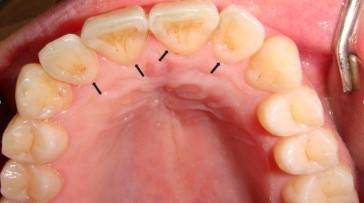

혹시 안쪽이 움푹 파여있진 않은가? 이런 치아를 삽처럼 생겼다고 해서 '삽 모양 앞니'라고 부르는데, 전 세계적으로 나타나지만 주로 아시아인에게 많이 나타나는 특징이다.

다만, 치아 뒷면 전체에 걸쳐 파이지 않고, 국소적으로 깊게 함몰되거나 작고 깊은 홈이 있다면 '절치 설면 소와'로 구조 이상일 수 있다. 황우진 홍보이사는 "절치 설면 소와일 때는 음식물이 끼기 쉬워, 충치 위험이 크다"고 했다. 이땐 치과에서 메우는 치료를 하기도 한다.

삽모양이 매우 깊어도 음식물이나 플라크가 남기 쉬운 환경일 수 있다. 황우진 홍보이사는 "음식물이 치아에 붙어있는 시간이 길수록 충치 생길 가능성이 커진다"며 "산도가 높은 음식을 먹지 않았다면 식사 후 바로 양치를 하고, 양치하기 어려운 상황이라면 입이라도 헹구는 게 좋다"고 했다. 삽모양이 깊은 치아는 양치할 때 치아 뒷쪽까지 부드럽게 꼼꼼히 닦아야 한다.